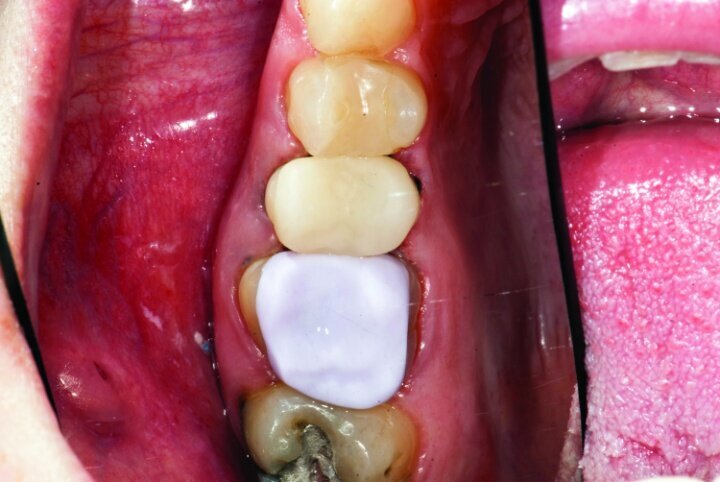

This patient presented for restorations of teeth #3 and #4 (Fig. 1a). Because of the size of the existing restorations, these teeth were diagnosed as structurally compromised (Figs. 1b, c). The prognosis without treatment was fair.

The restorations were to be completed with PlanScan chairside CAD/CAM technology in the same visit.

After gross occlusal reduction was completed, the remaining enamel ring was measured (Figs. 9a, b). The enamel rings were noted to be 1.5 mm, and the teeth were prepared for adhesively retained restorations. If the enamel rings were less than 1 mm, the teeth would have been prepared on the axial walls to create retention for cohesively retained crowns.